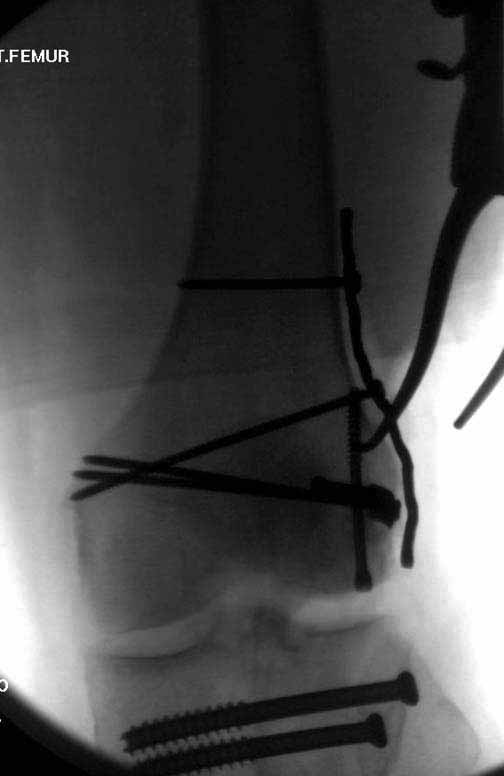

Пластину надо устанавливать на апексе перелома, иначе фрагмент начнет сползать. А на второй стороне, если имеется большой одиночный фрагмент тогда проблем не бывает, и их можно собрать компрессирующими винтами. Проблема наступает тогда когда многофрагментраность на латеральной стороне, где надо применить комбинированный метод, иногда несколькими пластинами. Или сменой позиции установки пластины, чтобы максимально прикрыть перелом и создать боковую поддержку.

Случаи могут быть разными и варианты фиксации могут быть различными. Это не эталон фиксации, и не каждый метод является "золотым стандартом". А “золотым” считается, когда внутрисуставной перелом отрепонирован на отлично и зафиксирован адекватно. Если возможно закрыто - хорошо, а так не надо искать только легкий закрытый путь, зная анатомию можно открывать, сколько надо!

Здесь пример медиальной пластины и латеральный комбинированный метод (у второго больного старый перелом тибиал плато, леченный где то и когда то)